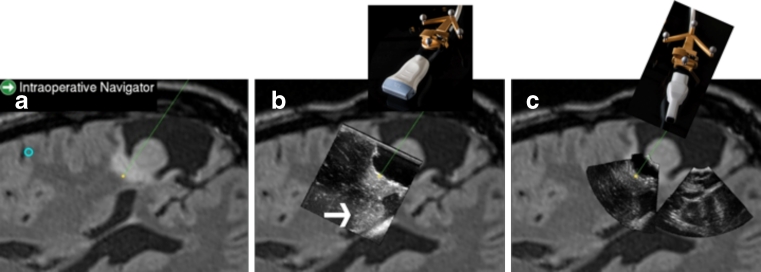

Fig. 3.

Screen display from a 3D ultrasound-based navigation system (SonoWand Invite) showing the image slice of preoperative MR (a) that is reformatted according to the orientation and angle of the navigation instrument. The corresponding reformatted image slice from an ultrasound volume that was acquired with a flat linear array probe (shown above for illustration) positioned at the brain cortex is shown in b. The reformatted ultrasound image slice from an ultrasound volume acquired with a small-sized phased array probe (shown above for illustration) inserted in the resection cavity (c). In b and c, the ultrasound volumes are acquired after part of the tumor is removed. Notice enhancement artefact in b marked with a bright arrow, which is not present in c where the data has been acquired with the probe in close distance to the bottom of the cavity